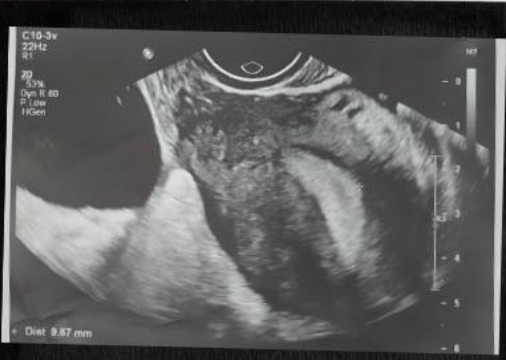

Bệnh viện Phụ Sản Hà Nội hội chẩn liên viện cứu thai nhi tim bẩm sinh phức tạp

Hội chẩn liên viện giữa các chuyên gia đa chuyên khoa giúp lập phương án chăm sóc, hồi sức và chuyển tuyến kịp thời cho thai nhi mắc dị tật tim bẩm sinh nguy cơ cao.